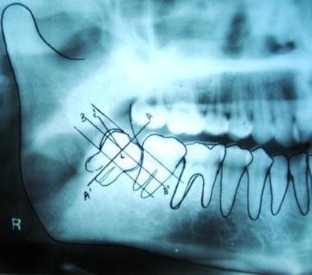

A Study on Dentigerous Cystic Changes with Radiographically Normal Impacted Mandibular Third Molars

Dentigerous cyst develops in the follicular tissue surrounding the impacted lower third molar. A study was carried out to know the incidence of Association of Dentigerous cyst with radiographically normal impacted lower third molars and to draw the attention of the Oral Surgeons towards the prophylactic removal of impacted third molars.

A prospective study was done on 30 patients with impacted lower third molars which were indicated for extraction. The follicle tissue surrounding the impacted tooth was subjected for histopathologic investigations. Only those teeth with a radiographic finding of pericoronal space of less than 2.5 mm were considered. Two Oral Pathologists reviewed the slides for any changes suggestive of cystic pathology.

Pathologic changes suggestive of Dentigerous cyst was found in 7 of the 30 follicular tissue sent for histopathologic testing. It was found to be statistically significant (P < 0.001).

This study shows statistically high incidence of Dentigerous cyst association with radiographically normal impacted lower third molar teeth. Hence the Oral and Maxillofacial surgeons should consider histopathologic evaluation and radiographic diagnosis in the management of impacted lower third molars. Prophylactic extractions of normal impacted lower third molars should be considered as a treatment option.